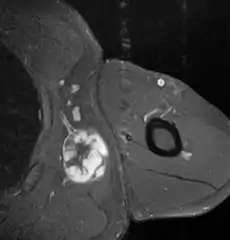

Medical imaging

Ultrasonography may not be able to distinguish a liposarcoma from a benign lipoma, and therefore, MRI is the initial imaging of choice.[4]

MRI of myxoid liposarcoma of high grade, in left axillary region of 40 year old man. Highlighted by the white color. Horizontal section.